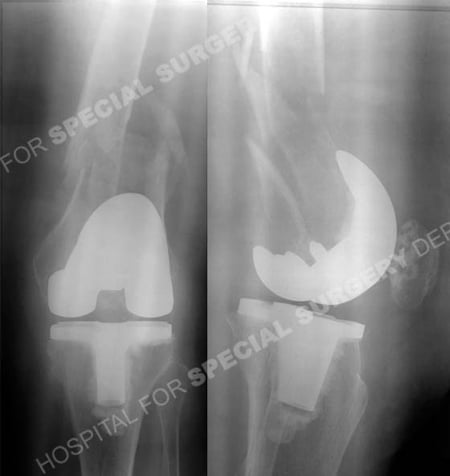

radiographs revealing a left-sided communited periprosthetic femur fracture from a case example presented by the orthopedic trauma service at Hospital for Special Surgery.

Anteroposterior and lateral injury radiographs revealing a left-sided comminuted periprosthetic femur fracture.